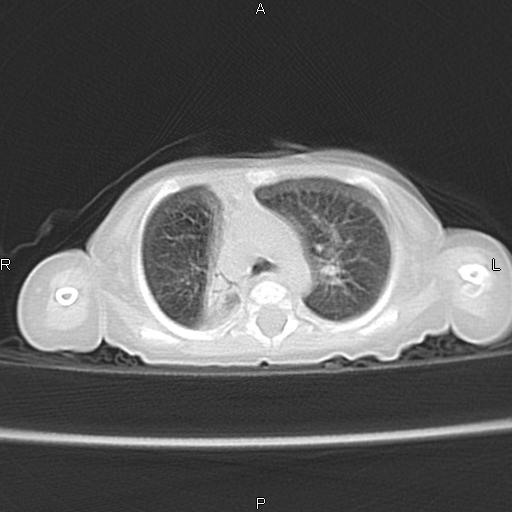

以下是引用aa13877358820在2010-7-26 12:35:00的发言:[br]男性,三个月,卧位胸片,咳嗽、气促、发热14天,两肺闻及细小水泡音。[br]